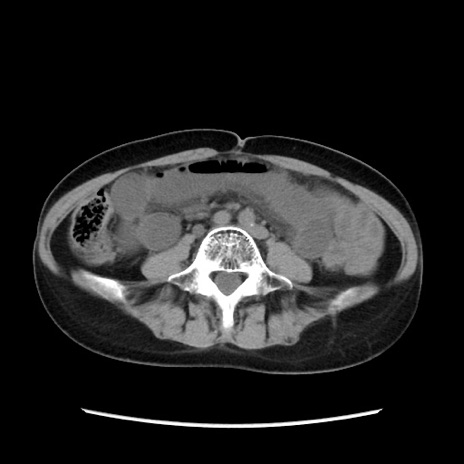

症例32(横断像)

【症例】40歳代 女性

【主訴】上腹部痛、嘔気・嘔吐

【現病歴】約9時間前頃から急に上腹部痛、嘔気、嘔吐が出現。改善しないため救急要請。

【既往歴】子宮頚癌(広汎子宮全摘術、放射線療法)、腸閉塞

【身体所見】腹部:平坦、軟、腸雑音亢進、上腹部を中心に腹部全体に圧痛あり。

【データ】WBC 8400、CRP 0.03